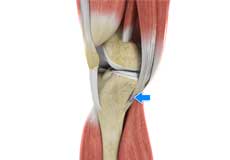

Ligaments of the Knee

Ligaments are tough bands of tissue that connect one bone to another bone. The ligaments of the knee stabilize the knee joint. There are two important groups of ligaments that hold the bones of the knee joint together, collateral and cruciate ligaments.

Collateral ligaments are present on either side of the knee. They prevent the knee from moving too far during side to side motion. The collateral ligament on the inside is called the medial collateral ligament (MCL) and the collateral ligament on the outside is called the lateral collateral ligament (LCL).

Cruciate ligaments, present inside the knee joint, control the back-and-forth motion of the knee. The cruciate ligament in the front of the knee is called anterior cruciate ligament (ACL) and the cruciate ligament in the back of the knee is called posterior cruciate ligament (PCL).